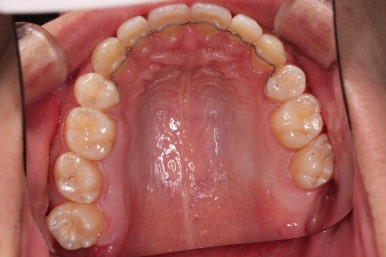

장치를 처음 부착한 모습입니다.

이번 환자분이 선택하신 장치는 데이몬 클리어라고 하는 자가결찰 세라믹 장치인데요.

흔히들 아시는 클리피씨 장치 등등에 비해 현존하는 브라켓 중에 가장 심미적인 장치입니다.

적절한 시기에 발치를 하고요.

순차적으로 장치를 붙여가며 치아를 가지런하게 합니다.

가지런하게 하는 단계를 거친 뒤,당기기 과정에 들어가는데요.

이 과정에서 입이 들어가는 양, 중앙선, 기울기, 앞니 각도 등등 많은 것을 신경써서 당기기를 해주는데요.

이 때 필요한 것이 미니스크류 입니다.

예전과는 다르게 미니스크류를 이용해서 좀 더 정교하고 고난이도의 치료가 가능해지게 된거죠.